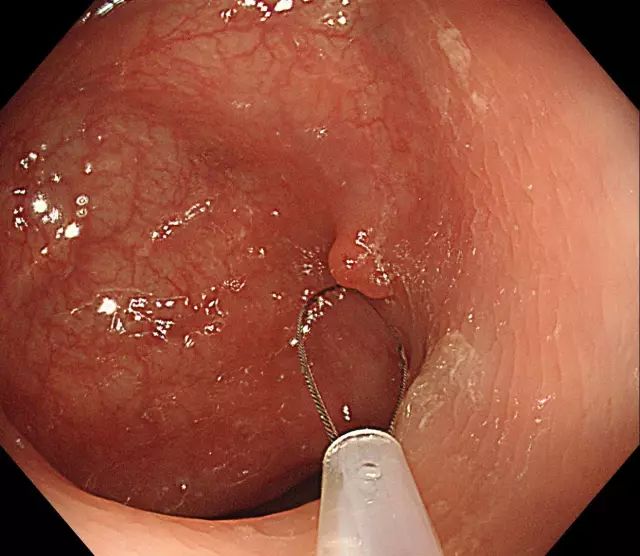

步骤四:轻轻向肠腔内提起息肉,使钢丝圈尽量远离肠壁黏膜。

图片

步骤五:在钢丝圈上脉冲式通高频电进行电灼烧,直至息肉根部被切断,息肉脱落。